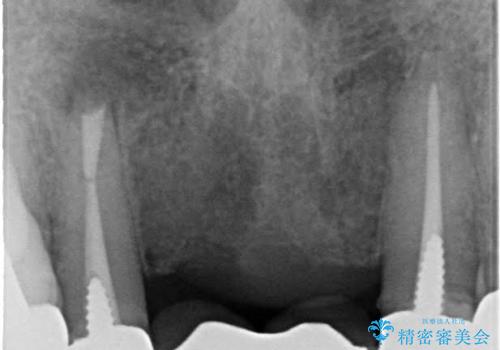

- 仮歯の製作、古い土台(メタルコア)の除去まで行い、根管治療は専門医に依頼

→根管治療終了後、ファイバーコアを築造し、新しいセラミックブリッジを製作した。

一見きれいにはいっているセラミックも、はずして中の状態をみるとひどいことが多い。これは、中の土台の状態や処理のクオリティは、短期的には問題を起こしづらく、患者さんには見えない部分だからです。